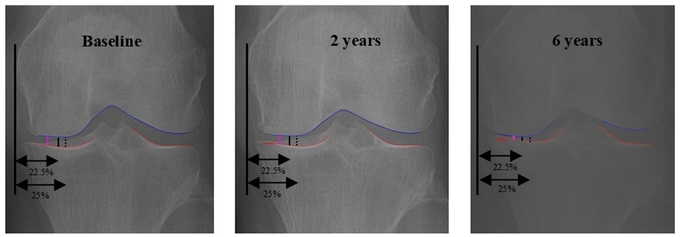

무릎 골관절염의 중증도는 보통 X-ray에서 허벅지뼈(대퇴골)와 정강이뼈(경골) 사이의 간격(JSW)을 측정해 평가한다.

기존에는 관절의 특정 위치를 고정해 간격을 쟀으나, 환자마다 다른 해부학적 특성과 비대칭적 마모 상태를 충분히 반영하지 못해 실제로 마모가 심한 부위를 놓칠 위험이 있었다.

반면 이번에 개발된 oJSW는 AI가 관절 내부를 자동으로 탐색해 가장 좁은 지점을 수직으로 측정하기 때문에 개인별 마모 상태를 정밀하게 반영할 수 있다.